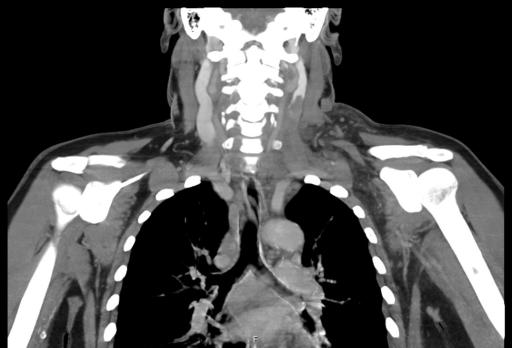

Het syndroom van Meigs is een zeldzame, goedaardige gynaecologische aandoening gekarakteriseerd door een trias van een ovariumfibroom, ascites en pleurale effusie, die verdwijnen na resectie van de adnexafwijking. Bij het pseudomeigssyndroom uiten de ovariumafwijkingen zich anders dan een fibroom. De casus die wij presenteren illustreert een bijzondere manifestatie van het pseudomeigssyndroom. Hoewel het syndroom bekendstaat om het benigne karakter, kan het zich presenteren met systemische manifestaties. Het gaat klassiek gepaard met respiratoire of abdominale klachten, een initiële uiting met een trombo-embolisch event is echter zeldzaam.